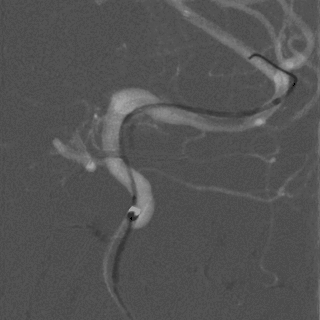

术后图像显示支架打开及贴壁良好。

术后工作位造影

术后侧位造影

术后正位造影

术后患者一般情况可,诉头疼,给予对症处理。神经查体:无阳性定位体征。给低分子肝素4100U皮下注射一次。继续口服阿司匹林100mg 1次/日,替格瑞洛90mg 2次/日。